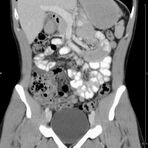

Abdomen (Bauch und Becken)

• Diagnostik von entzündlichen und tumorösen Erkrankungen der Bauchorgane

• Diagnostik von akuten Notfällen wie Darmverschluss, Hohlorganperforation oder Traumafolgen

• Darstellung der großen Gefäße zur Erkennung von Gefäßverschlüssen (z. B. Mesenterial - Arterienembolie oder Einengungen von Gefäßen (z. B. Nierenarterien)

• Darstellung und Therapieplanung von Aneurysmen (CT- Angiographie)

• Virtuelle Kolonographie zur Darstellung des Dickdarmes z. B. bei Kontraindikation zur Darm-Spiegelung oder nur unvollständig durchführbarer Koloskopie.